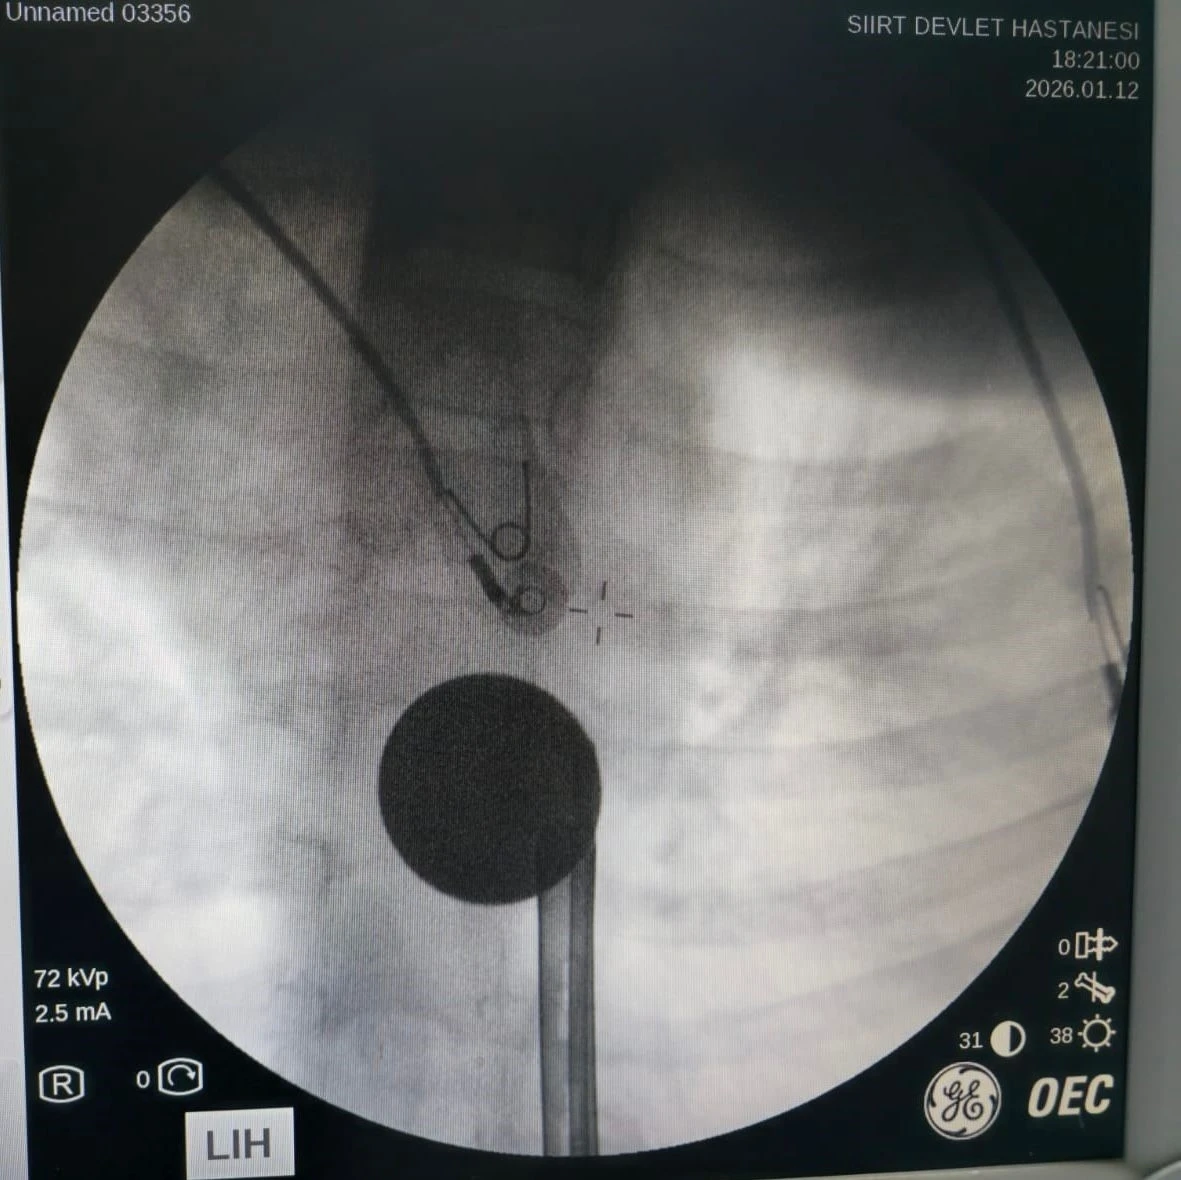

Siirt'te boğazına madeni 5 lira kaçan 8 yaşındaki çocuk, hastanede doktor müdahalesiyle kurtarıldı.

Yabancı cisim yutma şikayetiyle ailesi tarafından Siirt Eğitim ve Araştırma Hastanesine getirilen 8 yaşındaki Y.K., yapılan ilk değerlendirme ve görüntüleme tetkiklerinin ardından ilgili branşlarca operasyona alındı. Y.K.’nın yemek borusuna kadar ilerlediği tespit edilen madeni para, gastroenteroloji uzmanı Dr. Yaren Dirik ve kulak burun boğaz hekimi Yasin Gökçınar tarafından müdahale edilerek çıkartıldı. Operasyonun ardından bir süre gözlem altında tutulan Y.K., tedavisinin tamamlanmasıyla taburcu edildi.

Siirt Eğitim ve Araştırma Hastanesi Başhekim Yardımcısı Uzman Dr. Burak Özkan, çocuk hastalarda yabancı cisim yutma vakalarının ciddi riskler oluşturabileceğini söyledi. Uzm. Dr. Özkan, "Hastanemize başvuran 8 yaşındaki hastamızın yemek borusuna kaçan madeni para, gastroenteroloji ve KBB ekiplerimizin koordineli ve titiz çalışmasıyla herhangi bir komplikasyona yol açmadan başarılı bir şekilde çıkarılmıştır. Operasyon süreci sorunsuz geçmiş olup hastamızın genel durumu iyidir" dedi.